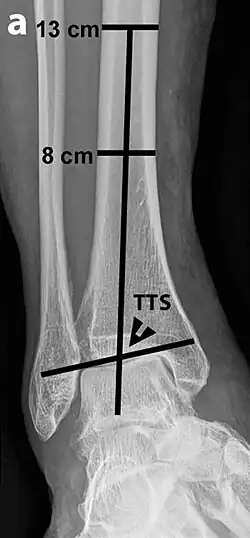

Varus or valgus deformity, if suspected, can be measured with the frontal tibiotalar surface angle (TTS), formed by the mid-longitudinal tibial axis (such as through a line bisecting the tibia at 8 and 13 cm above the tibial plafond) and the talar surface.[25] An angle of less than 84 degrees is regarded as talipes varus, and an angle of more than 94 degrees is regarded as talipes valgus.[26]